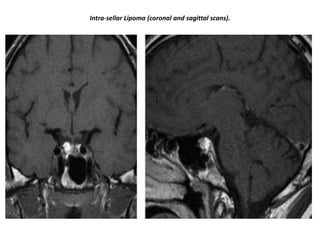

Intra-sellar Lipoma (coronal and sagittal scans).

Intra-sellar Lipoma (coronaland sagittal scans).